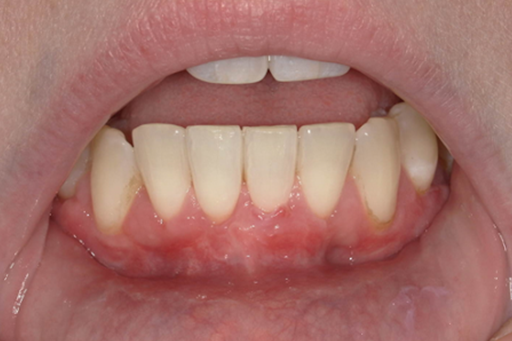

See What’s Possible

Explore the real transformations of patients who trusted us with their smiles.

Gingival recession